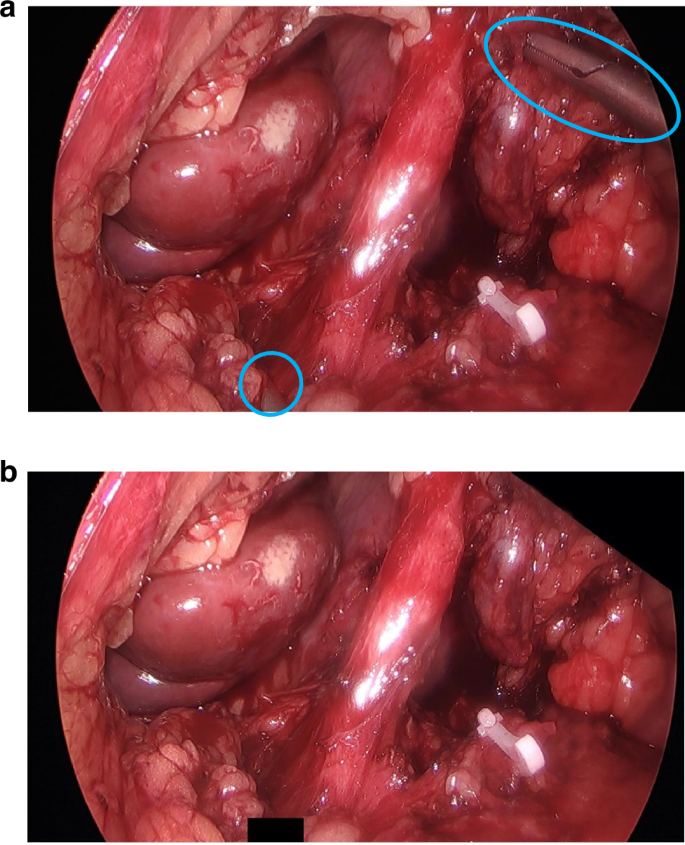

Another problem was that some photographs revealed the treatment allocation (i.e. whether it was OO or LAO). Common reasons for this were visible procedure-specific surgical instruments or gloved hands (indicating OO). Post-production editing was undertaken to crop identifiers out of view to ensure that assessors could remain blinded (Fig. 1) to the randomised allocation. Occasionally, this was not possible due to the proximity of the identifiers to important anatomical structures. In this scenario, we placed ‘black boxes’ over the identifiers to mask them (Fig. 2). The shape and/or size of the black boxes was purposefully changed throughout to avoid identification of procedure type related to the position of the instruments or hands.

Image a shows the identifiable objects requiring anonymisation, and image b shows the black boxes to achieve this.